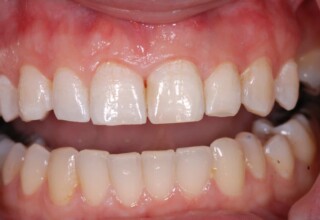

Οι όψεις ρητίνης προσφέρουν έναν οικονομικό τρόπο αισθητικής βελτίωσης της εμφάνισης των προσθίων δοντιών ενίοτε και των προγομφίων. Οι δυνατότητες τους πολλές, μπορούν να κάνουν και θαύματα! Ο μονός περιορισμός η κλινική ευχέρεια και η φαντασία του επεμβαίνοντος. Σε αυτήν την ασθενή οι τέσσερεις άνω τομείς είχαν ο καθένας το δικό του πρόβλημα(δυσχρωμία, απόκλιση) και επιπλέον: διαστήματα, πολλαπλές αποχρώσεις, κακή σχέση μεταξύ τους και με τα ούλα. Αποκαταστάθηκαν με τέσσερεις άμεσες όψεις ρητίνης (η μια πάνω σε στεφάνη πορσελάνης εμφυτεύματος!!!) οι οποίες κατασκευάστηκαν ενδοστοματικά!